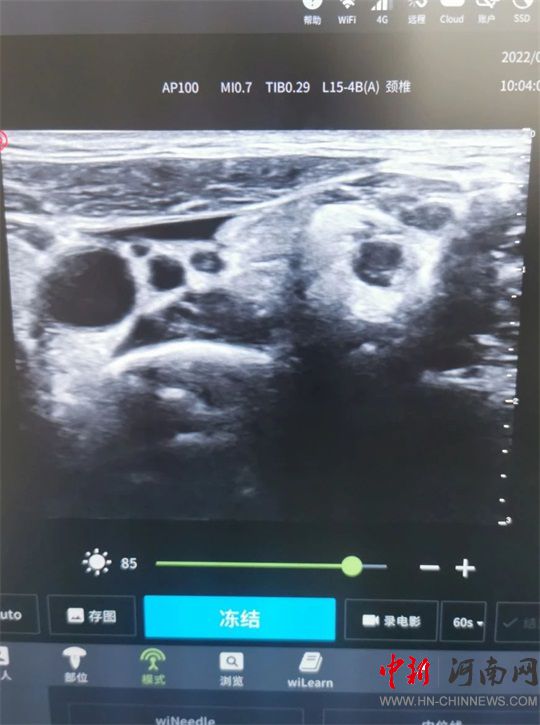

并進(jìn)行超聲引導(dǎo)下

星狀神經(jīng)節(jié)阻滯治療

通過(guò)超聲定位

頸6椎體橫突

穿刺針避開(kāi)神經(jīng)、血管

抵達(dá)頸動(dòng)脈鞘外

注入藥液

治療完成